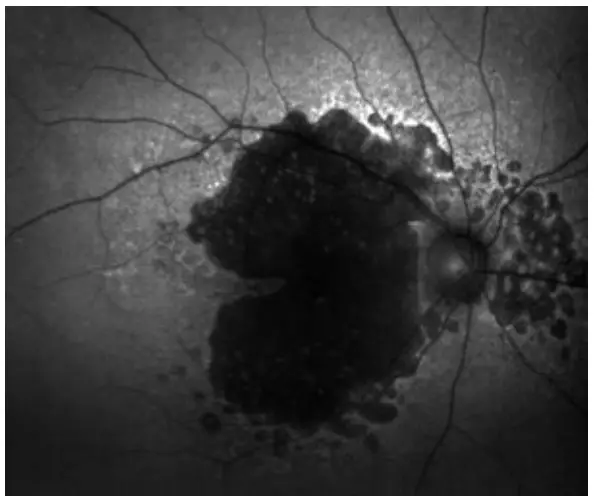

Fundus Autofluorescence (FAF)

Fundus autofluorescence images allow clinicians to visualize lipofuscin fluorescence in the retinal pigment epithelium (RPE), an indicator of RPE health. Healthy RPE appears as a uniform gray color on FAF images. In general, hyper-auto fluorescence (bright) indicates RPE damage, and hypo autofluorescence (dark) indicates dead or absent RPE. FAF-Blue images have been shown to reveal early RPE disruption in macular degeneration and predict progression of geographic atrophy. FAF-Green images may be less affected by media opacities such as nuclear sclerotic cataracts.

- Fundus autofluorescence-Blue (FAF-Blue) image of geographic atrophy.

- Fundus autofluorescence-Green (FAF-Green) image of dry age-related macular degeneration.